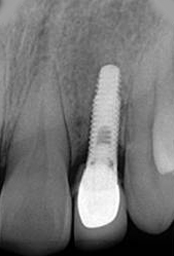

X-ray of Implant + Abutment

Single Tooth Implant